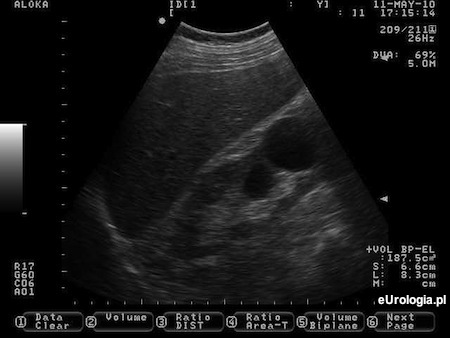

Fot. Torbiel prosta prawej nerki - obraz USG.